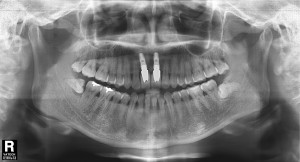

김정아 앞니 치료후

앞니 임플란트 잘 못 시술 받게 되면 많은 고통과 재수술의 어려움이 따릅니다.

앞니 임플란트 첫 단추가 잘 채워져야 나머지 단추가 맞게 채워지듯이, 앞니 임플란트 시술을 위한 치과 선택도 잘 하셔야겠죠!

앞니 임플란트 상담은 앞니 임플란트 전문 치과인 파크에비뉴치과 (02)566-6628로 문의 주시면 앞니 임플란트 실패하지 않고 만족 스러운 결과를 약속드립니다.